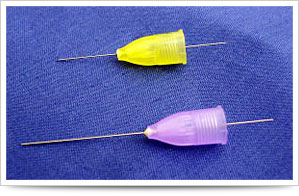

針は細ければ細いほど痛みは抑えられます。

針は細ければ細いほど痛みは抑えられます。

当院では極細の針を使用しています。